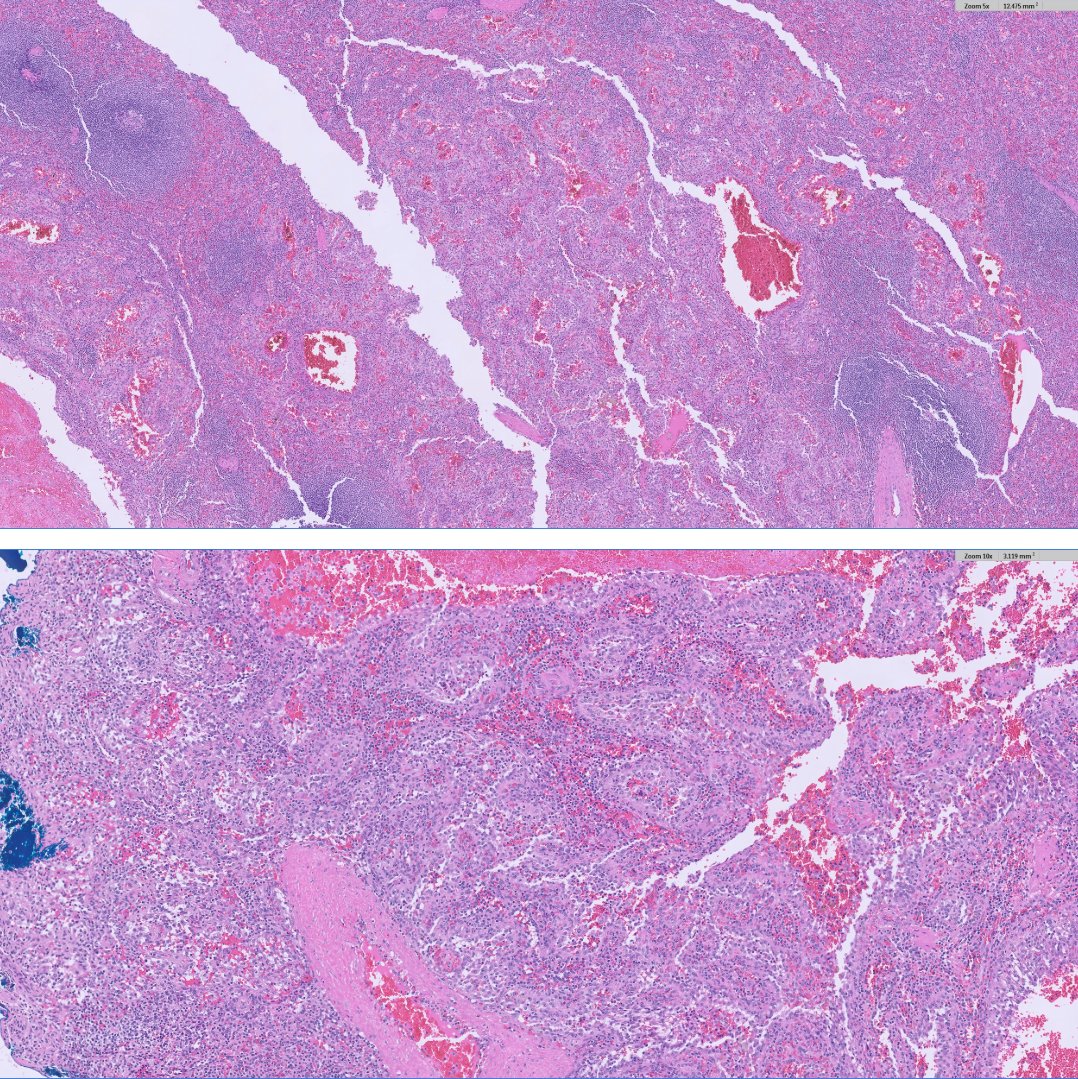

💎 Papillary Renal Cell Carcinoma (PRCC) in Acquired Cystic Kidney Disease ⚓️ Definition: PRCC is a malignant epithelial tumour with papillary or tubulopapillary architecture — the second most common renal cell carcinoma (13–20%). ⚓️ Association: Seen in patients with end-stage